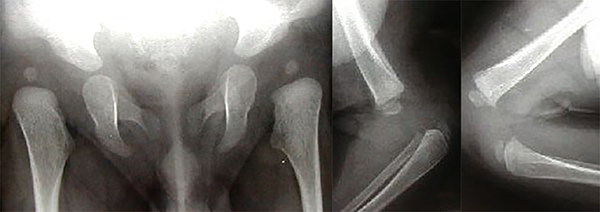

El paciente es llevado a consulta a los cuatro meses con un cuadro de genu recurvatum congénito bilateral, luxación congénita de cadera bilateral, astrágalo vertical derecho, hipertelorismo con frente prominente y puente nasal ancho (figs. 1 y 2).

Figura 1: Rx de caderas luxadas. Rx de luxación anterior de ambas rodillas.

Figura 2: RM en la que se ve la luxación congénita de ambas rodillas.